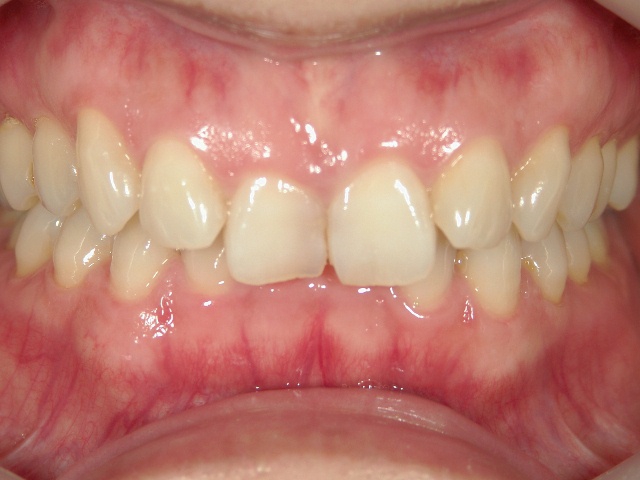

矯正歯科 治療前

全顎ワイヤー矯正 症例(2)

36歳女性 磐田市

在住

治療期間2年6

ヶ月